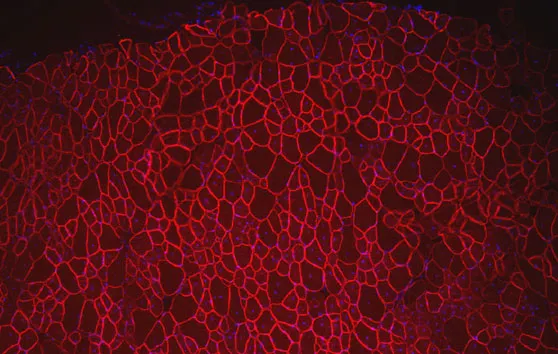

Myopathies centronuléaires : un 7e atelier ENMC

Le compte rendu du 198e workshop ENMC, correspondant au 7e atelier exclusivement consacré aux myopathies centronucléaires, est paru en août 2013.